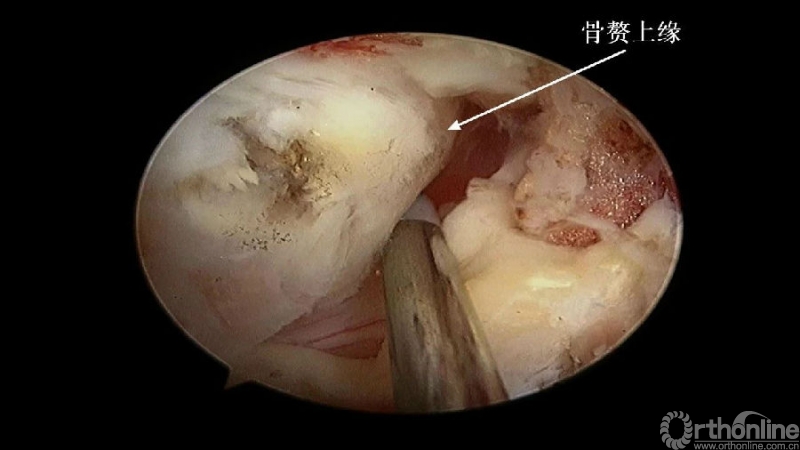

入院查体患者四肢肌张力高,双侧hoffman阳性。CT及MRI检查提示C4/5左侧关节突内缘有一巨大骨块(15mm*16mm),相应节段椎管严重狭窄。椎管内骨块的前端还有一游离骨块。

2. 术中骨赘的界限?